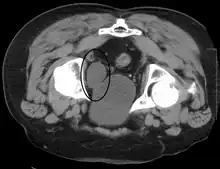

Cancer

Cancer of the bladder is known as bladder cancer. It is usually due to cancer of the urothelium, the cells that line the surface of the bladder. Bladder cancer is more common after the age of 40, and more common in men than women;[33] other risk factors include smoking and exposure to dyes such as aromatic amines and aldehydes.[33] When cancer is present, the most common symptom in an affected person is blood in the urine; a physical medical examination may be otherwise normal, except in late disease.[33] Bladder cancer is most often due to cancer of the cells lining the ureter, called transitional cell carcinoma, although it can more rarely occur as a squamous cell carcinoma if the type of cells lining the urethra have changed due to chronic inflammation, such as due to stones or schistosomiasis.[33]

Investigations performed usually include collecting a sample of urine for an inspection for malignant cells under a microscope, called cytology, as well as medical imaging by a CT urogram or ultrasound.[33] If a concerning lesion is seen, a flexible camera may be inserted into the bladder, called cystoscopy, in order to view the lesion and take a biopsy, and a CT scan will be performed of other body parts (a CT scan of the chest, abdomen and pelvis) to look for additional metastatic lesions.[33]

Treatment depends on the cancer's stage. Cancer present only in the bladder may be removed surgically via cystoscopy; an injection of the chemotherapeutic mitomycin C may be performed at the same time.[33] Cancers that are high grade may be treated with an injection of the BCG vaccine into the bladder wall, and may require surgical removal if it does not resolve.[33] Cancer that is invading through the bladder wall may be managed by complete surgical removal of the bladder (radical cystectomy), with the ureters diverted into a segment of part of ileum connected to a stoma bag on the skin.[33] Prognosis can vary markedly depending on the cancer's stage and grade, with a better prognosis associated with tumours found only in the bladder, that are low grade, that do not invade through the bladder wall, and that is papillary in visual appearance.[33]

Some forms of medical imaging exist to visualise the bladder. A bladder ultrasound may be conducted to view how much urine is within the bladder, indicating urinary retention. A urinary tract ultrasound, conducted by a more trained operator, may be conducted to view whether there are stones, tumours or sites of obstruction within the bladder and urinary tract. A CT scan may also be ordered.